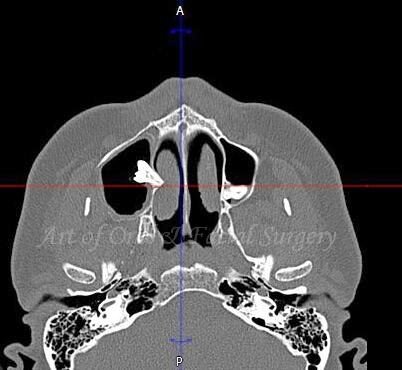

Проведено КЛКТ.

КЛКТ  - аксиальный реформат

И тут сюрприз. На серии томограмм видно, что ретенированный 18 расположен в области медиальной стенки гайморовой пазухи. Никаких признаков новообразования (изменения плотности) в области полости пазухи не определяется. Резорбция корней зубов 1.7, 1.8.